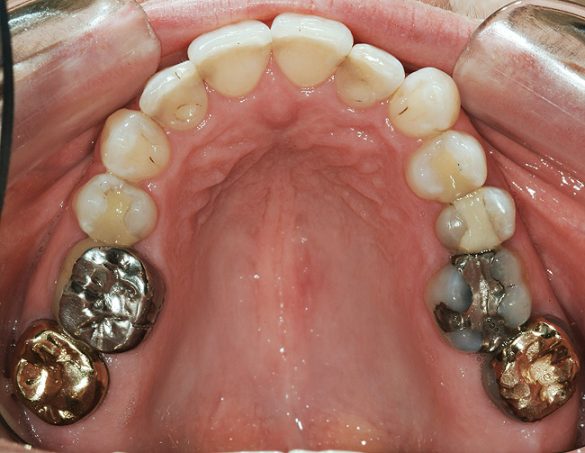

O pacientă în vârstă de 44 de ani s-a prezentat pentru evaluarea şi îmbunătăţirea zâmbetului ei. Acuza principală era reprezentată de afişarea neatractivă a coroanelor posterioare din aur, asociată cu petele albe inestetice de pe dinţii frontali (fig. 1, 2). Scopul ei convingător pentru solicitarea tratamentului a fost acela de a dobândi un „zâmbet deosebit”.

S-au constatat carii dentare active la nivelul 1.7., 4.6. şi 4.4. Dinţii 1.7., 1.6., 2.4.-2.7., 4.4., 4.7. prezentau restaurări cu adaptare defectuoasă. Dinţii 1.7.-1.5., 2.5.-2.7., 3.5.-3.7., 4.5.-4.7. au fost notaţi cu structură compromisă datorită dimensiunii, tipului şi profunzimii restaurărilor. În plus, segmentul dentar 3.2.-4.2. prezenta semne precoce de eroziune chimică la nivelul muchiilor incizale. Corespunzător 1.6. s-a obiectivat o exostoză osoasă pe versantul vestibular (fig. 5), generând o înălţime scurtă a coroanei clinice şi un compromis restaurator ulterior.

FUNCŢIONAL: La majoritatea dinţilor posteriori ai pacientei ce erau restauraţi cu coroane (fig. 6, 7) era importantă interpretarea minuţioasă a istoricului pacientei şi a rezultatelor evaluării ocluzale. Coroanele din aur de la nivelul 1.7. şi 1.4. prezentau orificii de uzură pe suprafeţele ocluzale, cu semne de minimă uzură pe celelalte coroane posterioare şi la dentiţia naturală. Era evidentă o uzură moderată pe coroana din aur a molarului 4.7.